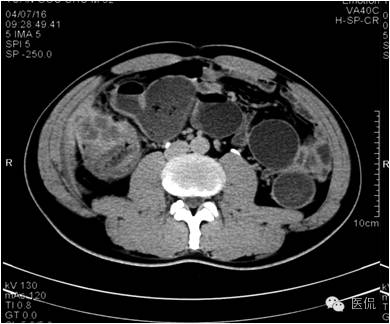

延迟期密度略有下降,但仍有强化,形态不规则。

手术病理诊断:

肝炎性假瘤,侵及周围结肠和腹壁,浸润组织有水肿,粘连。